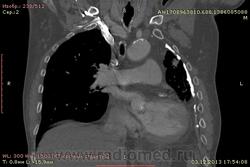

Доброго времени суток уважаемые форумчани! :)Провели исследование КТ грудной клетки с контрастированием, для выявления аневризмы грудного отдела аорты. В результате увидели это:

??? Аневризму честно не вижу (мало опыта в определении аневризм). Тромбоз в бассейне верхней полой вены. В левом легком обызвествленные плевральные шварты? как исход осумкованного плеврита неизвестной давности?

намерил аорту, всё таки есть аневризматическое расширение луковицы

Ребята, вы что, какая жидкость? Чистая известь, посмотрите в костном окне. Отставить натив (в данном случае, хотя для аневризм он обычно нужен). Отставить тромбоз верхней полой вены (потоковые артефакты, не дело вены в артериальную фазу оценивать). Отставить аневризму  аорты, поперчник восходящего отдела на уровне легочного ствола 42мм. А вот легочная гипертензия, здравствуй: поперечник легочного ствола - 37мм, ПЛА - 25мм, ЛЛА - 25мм, НАо - 25-34мм.